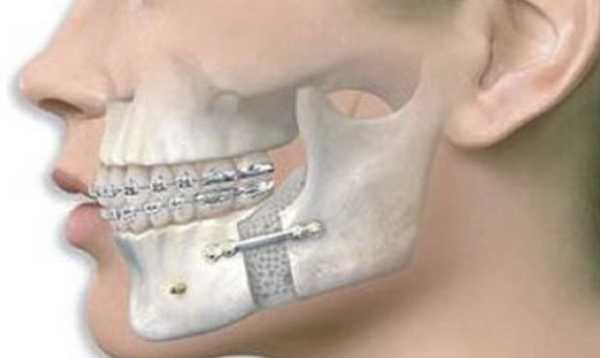

Остеотомия нижней челюсти предусматривает костные разрезы за коренными зубами вдоль челюсти вниз, чтобы нижняя челюсть могла двигаться как единое целое. В результате такой манипуляции нижняя челюсть, с помощью титановой пластины, плавно перемещается на новое место.

Фрагменту задают нужное положение, крепят прочными пластинами из титанового сплава и оставляют в таком состоянии до того момента, когда вырастет новая твердая ткань.

Нижняя челюсть. Процедура выполняется под местной анестезией. Выполняют рассечение слизистой и надрез костной ткани позади коренных зубных элементов. Костную ткань распиливают, раздвигают и фиксируют при помощи пластин в требуемом положении.